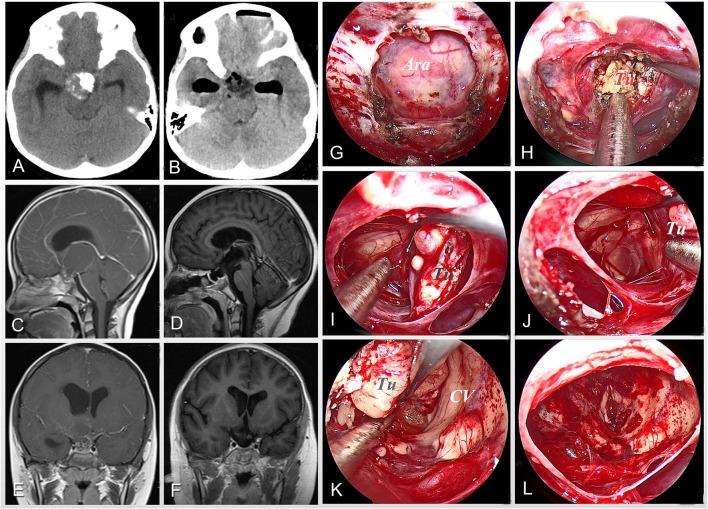

扩大神经内镜经鼻入路切除儿童颅咽管瘤

Extended Neuroendoscopic Endonasal Approach for Resection of Craniopharyngioma in Children.

To explore the surgical approach and technique of neuroendoscopic endonasal resection of pediatric craniopharyngiomas and to further evaluate its safety and effect in children.

METHODS

The clinical data of 8 children with craniopharyngiomas who were surgically treated by neuroendoscopy through an extended endonasal approach in our center from 2018 to 2021 were retrospectively analyzed. The related surgical approach and technique were evaluated to improve the surgical results and further reduce the surgical complications when removing craniopharyngioma in children.

RESULTS

All 8 patients achieved a gross-total resection of the tumor under neuroendoscopy. Postoperatively, 2 cases of transient hyperthermia and 4 cases of transient hyper- and/or hyponatremia occurred within the first 2 weeks, all of which were quickly controlled. Seven patients had symptoms of diabetes insipidus to varying degrees after the operation, and 4 of them improved within 1-3 months after surgery, but 3 cases still needed oral pituitrin. There were no cases of coma or death, leakage of cerebrospinal fluid, or severe electrolyte imbalance after surgery. During the postoperative follow-up of 3 months to 2 years, no tumor recurrence was found. Among the 7 patients who suffered postoperative neuroendocrine deficiencies, 3 patients were found to be temporary during the follow-up, but 4 patients still required hormone replacement therapy. Particularly, postoperative visual deterioration and olfactory defect that occurred in patients were all improved during follow-up periods. In addition, 4 cases of obesity were noted at the last follow-up.

CONCLUSIONS

Extended neuroendoscopic endonasal resection of craniopharyngiomas may be used as a safe and effective approach for children. Due to the poor pneumatization of the sphenoid sinus and worse compliance of treatment in children, surgical techniques of exposing the sellar region, removing the tumor, and reconstructing the skull base, as well as postoperative management of patients was proposed. However, due to the limited surgical cases in the study, the surgical safety and effects of the extended neuroendoscopic endonasal approach for children with craniopharyngiomas need to be further studied in the future.